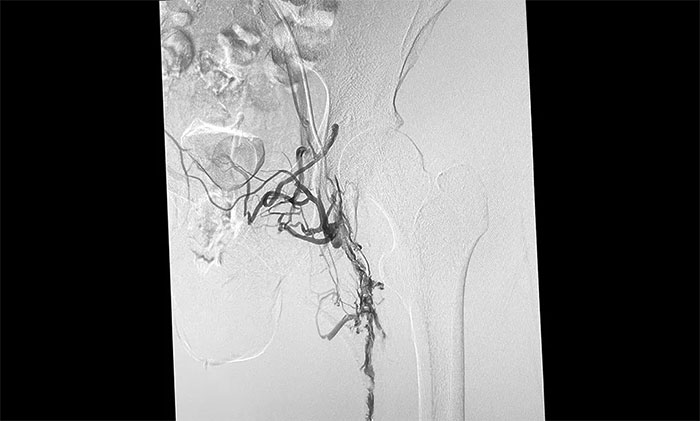

▲ 下肢深静脉血栓形式

▲ 下肢静脉血管顺利再通

12月15日,席刚明教授在王贵平博士及介入团队协助下顺利行将一个形似伞状的人工滤器经患者右侧股静脉穿刺迅速置入肾静脉下方,“网”住了通往心血管和肺部的致命栓子,阻挡血液栓子进入肺动脉,及时挽救了患者生命。之后对病变血管进行了血栓抽吸术,及接触性溶栓,抽出了大量血栓,复查下肢造影示血栓基本消失,下肢静脉血管再通,整个手术顺利完成。术后,患者下肢肿胀好转。